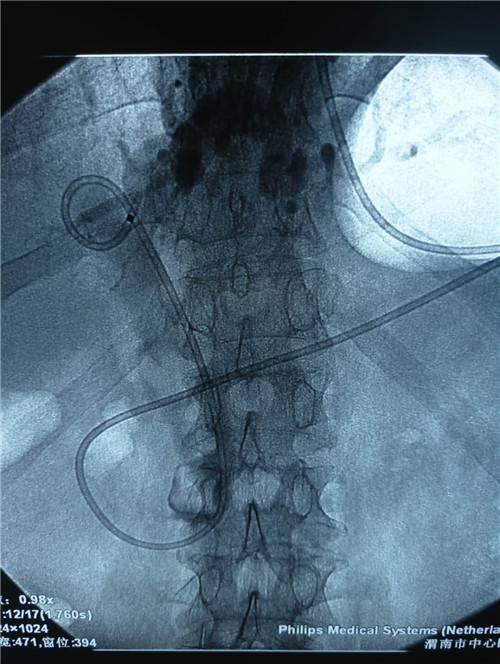

该患者男性,81岁,体温持续40摄氏度,血压80/50mmHg,心率120次/分,有结核病史,曾患脑梗死,右侧肢体活动障碍,精神极差,该手术风险极高,胆总管内多发大结石、急性化脓性胆管炎;这种状态下如果行开腹手术,死亡率极高。普外科史和平主任、王旭、吴云龙医生讨论后决定先行ERCP下鼻胆管引流术,首先缓解患者胆管炎症状,待患者症状减轻,生命体征平稳后再行下一步治疗。

曹鹏医生进十二指肠镜后看到肿大的乳头,利用切开刀+导丝超选进入胆管,行十二指肠乳头切开,随即大量脓性胆汁流出,并迅速留置鼻胆管。功夫不负有心人,终于,在主管护师许晓庆、护士王欣的配合下,又成功挽救了一名病患的生命,同时也彰显了市中心医院消化内镜中心医护人员极高的专业素养和娴熟的业务能力。